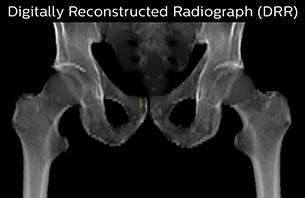

Using the mDIXON and 3D bFFE images, the RT planner marks the position of the nickel-titanium fiducial markers, and contours are transferred to the digitally reconstructed radiographs (DRRs). Reference image matching is based on these markers. “In the rare cases, where visualization of the fiducial markers fails, we do a CT to confirm their location,” Dr. Keyriläinen notes.

MR-only simulation workflow The 3D T1W FFE mDIXON sequence provides in-phase, water and fat images in one acquisition. Target and organs-at-risk are delineated on the 3D T2W TSE images. Prostate GTV is shown in orange, PTV in purple. The 3D bFFE sequence is used by the planner to mark the position of the fiducial markers (gold anchors) and contours are transferred to the digitally reconstructed radiographs (DRRs).

Based on the 3D T1W mDIXON images, MR-based density maps (MRCAT) are automatically generated. The VMAT (Volumetric Modulated Arc Therapy) plan is generated in TPS, based on MRCAT as primary image set. During the commissioning phase, dosimetric agreement between MRCAT-based and CT-based dose plans was studied and differences in the PTV dose were found to be minimal (<1% for most patients). Average difference in PTV mean values was 0.8% over the study group (n=62).